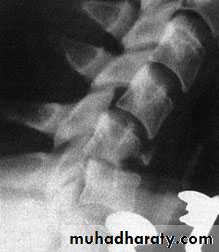

Wedge compression fracture

A pure flexion injury results in a wedge compressionfracture of the vertebral body .The middle

and posterior elements remain intact and the

injury is stable. All that is needed is a comfortable collar for 6–12 weeks.

. Diagnosis.

1. The x-ray should be carefully

examined to exclude damage to the middle column

and posterior displacement of the vertebral body

fragment, i.e. features of a burst fracture (see below)

which is potentially dangerous. If there is the least doubt

2. an axial CT

3. MRI should be obtained.